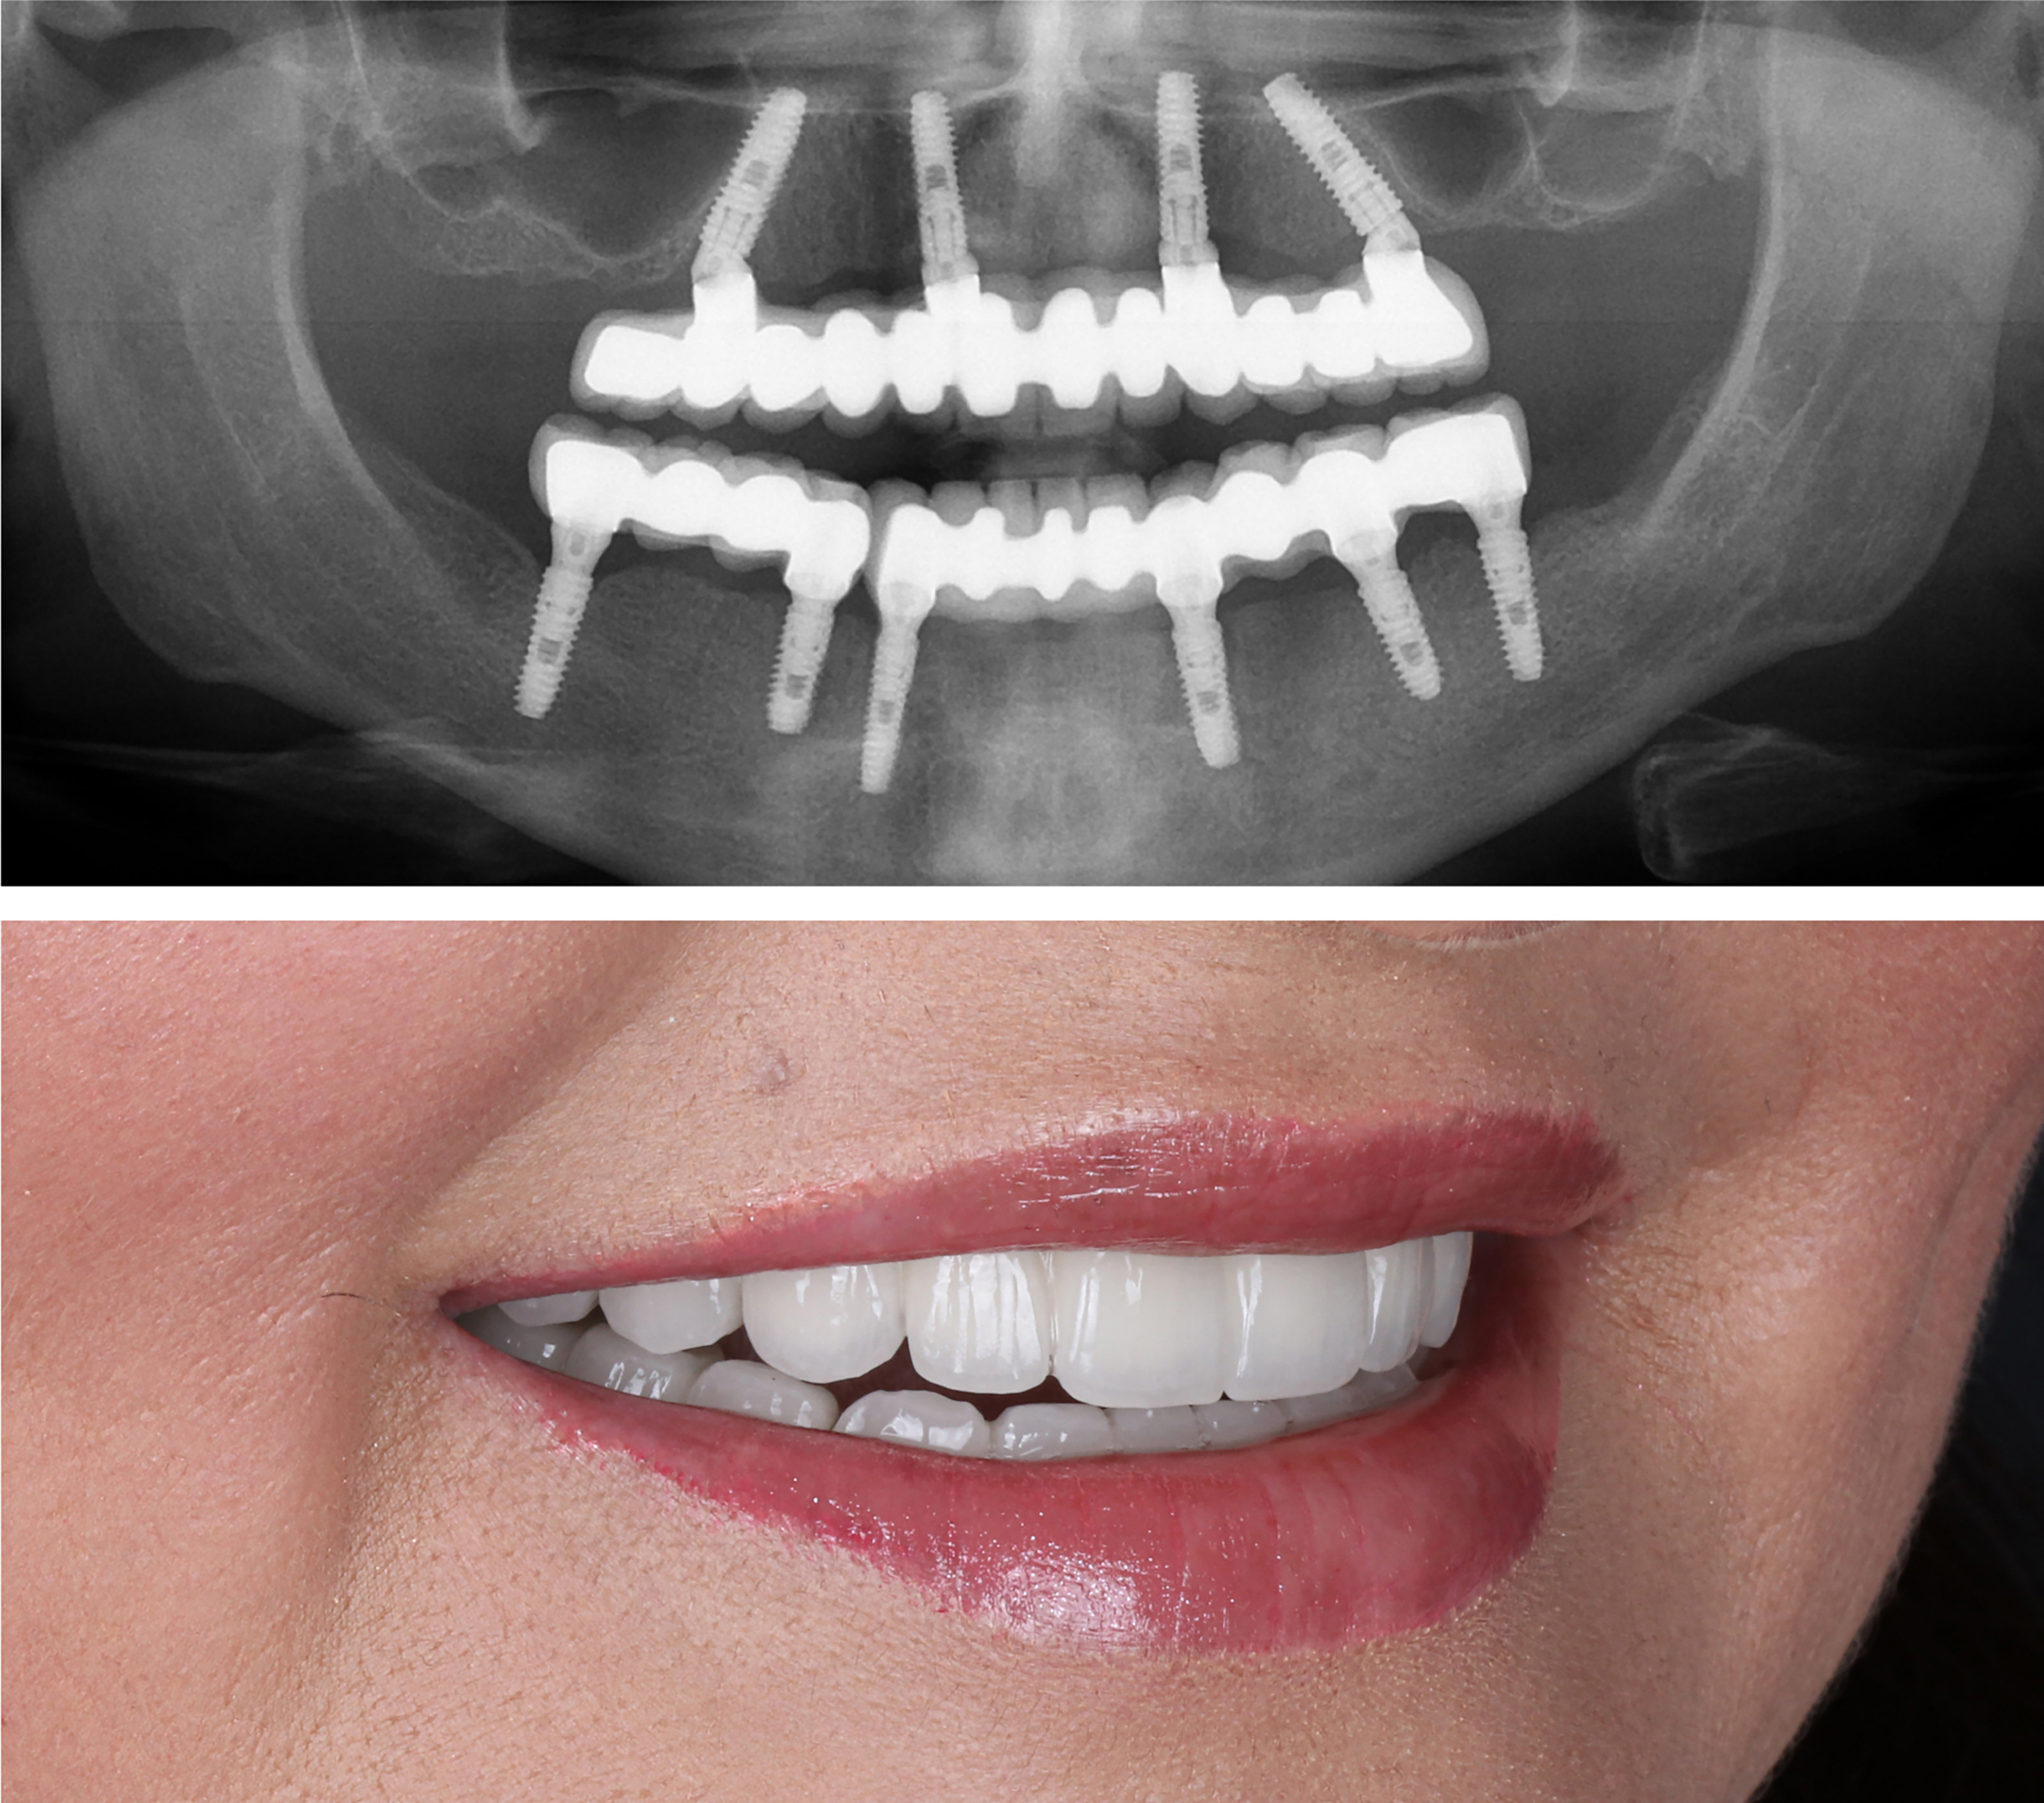

Example transformations achievable with dental implants

Includes surgical placement of 4 to 6 implants.

Includes final ultra aesthetic teeth.

Includes final zirconia teeth.